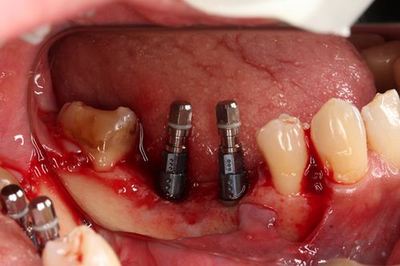

インプラントはスイスのストローマンインプラントです。

無事埋入を終えました。

インプラント挿入ジグを外しました。